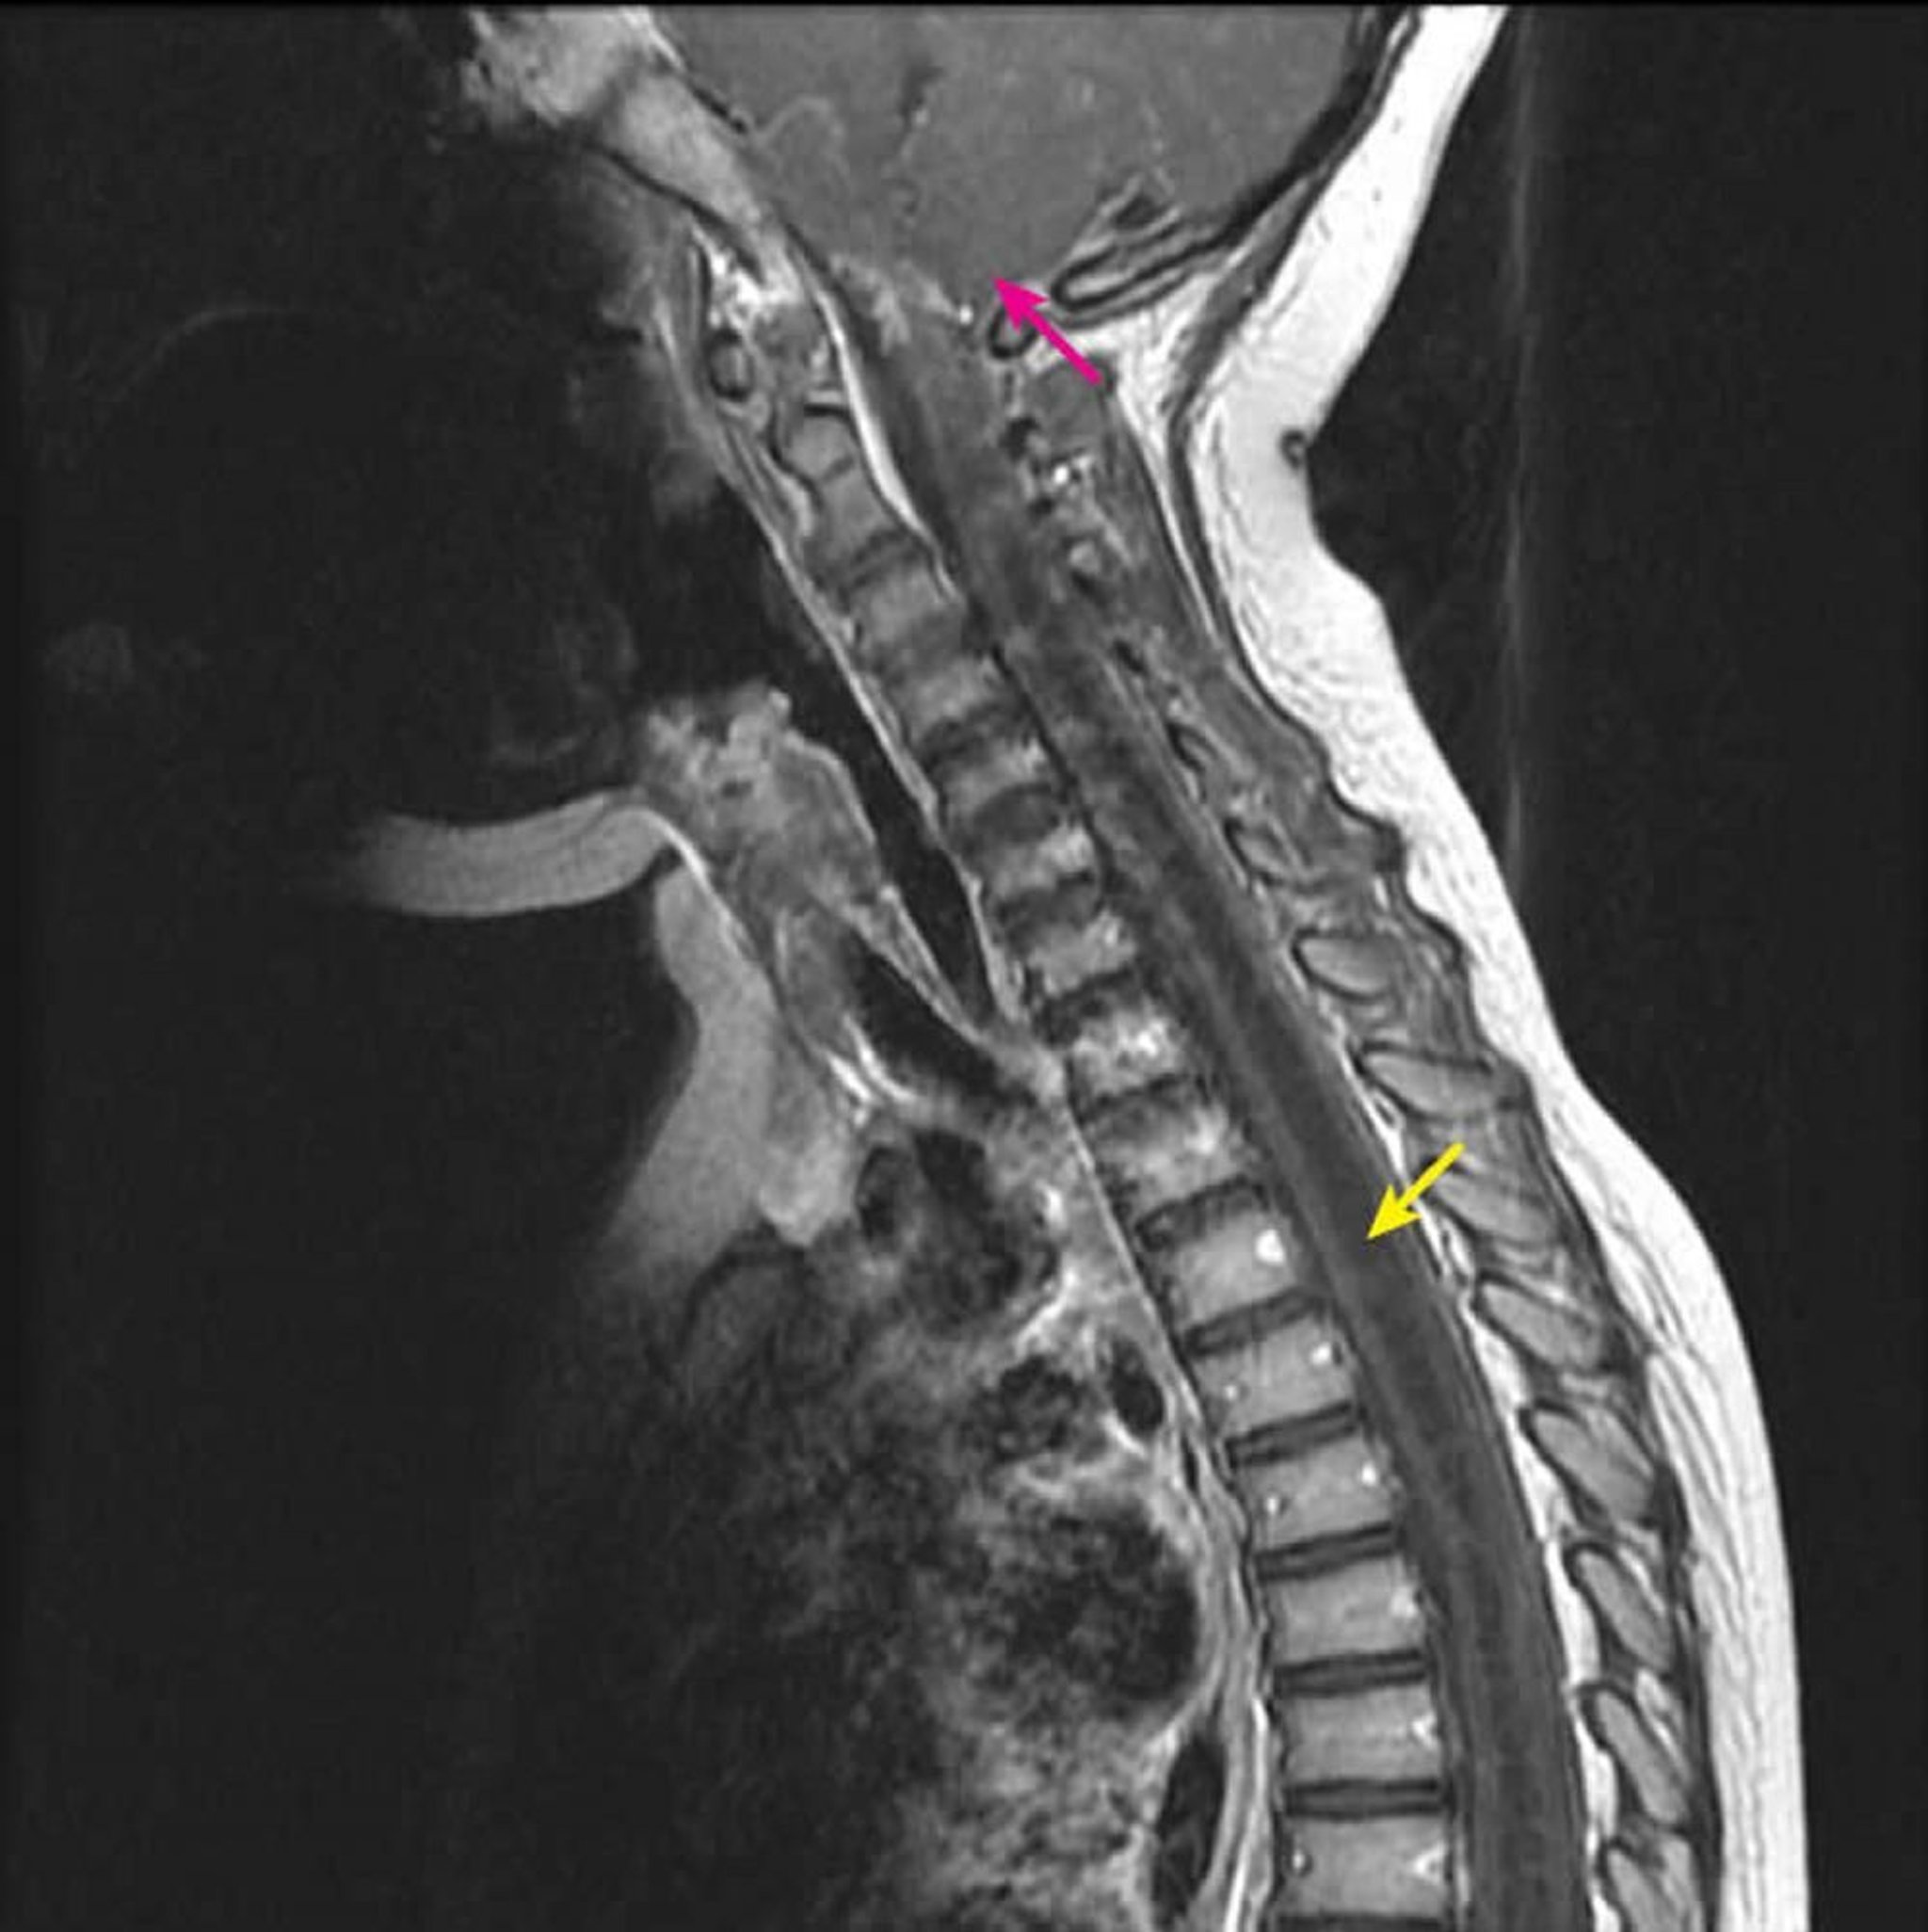

La RM sagital en T1 poscontraste muestra una gran cavidad dentro de la médula espinal hipoinensa en T1 característica de la cavidad siringomiélica (flecha amarilla). Se extiende desde el nivel cervical C2-C3 hacia abajo en un niño con una malformación de Chiari tipo I conocida (flecha rosa). Este hallazgo se define como siringohidromielia porque la siringomielia (una cavidad de la médula espinal excéntrica) no puede ser diferenciada de la hidromielia (una cavidad de la médula espinal central) por las imágenes.

Courtesy of John Tsiouris, MD, Division of Neuroradiology, New York–Presbyterian Hospital/Weill Cornell Medical Center.